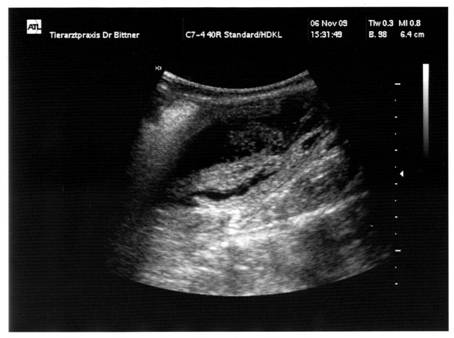

26. 1 0.2009  Tag 25  |

:  |

MiniFee  |

hatte heute endlich ihren Ultraschall-Termin … … der Tierarzt hat einen

Embryo klar erkannt. Auf Grund des relativ

niedrigen Progesteron-Wertes zum Zeitpunkt der Deckung wird in 10 Tagen noch

einmal ein Ultraschall gemacht. Ich bin so gespannt, ob es bei MiniFee’s Trächtigkeit bleibt !!!   |